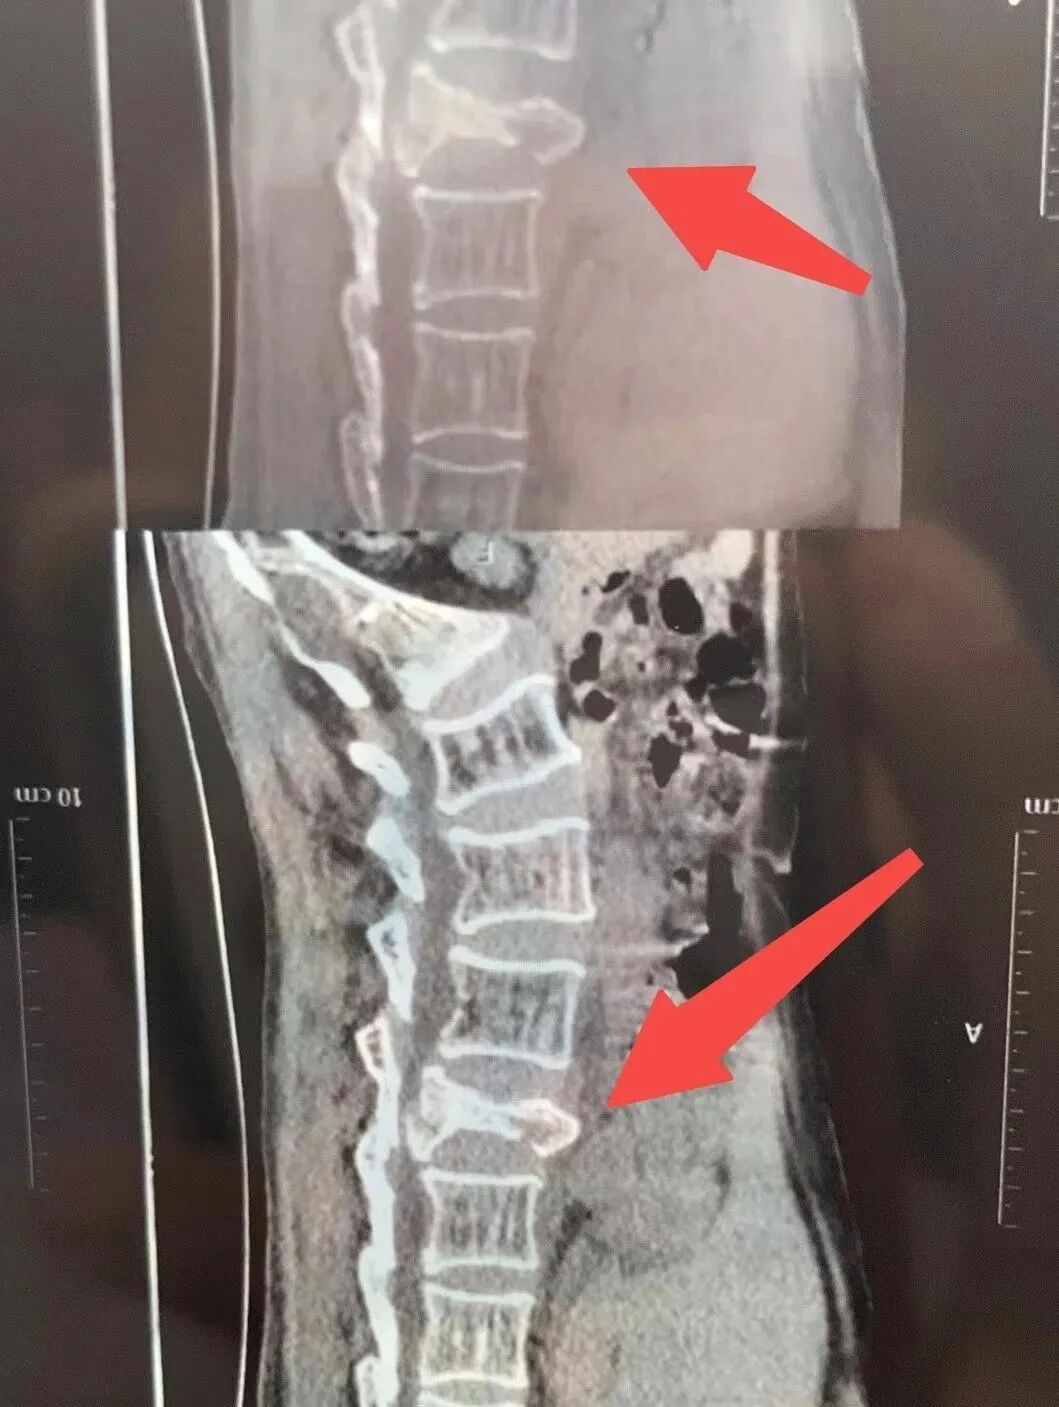

医院于2023.9.2凌晨出报告:腰椎三处骨折,爆裂性骨折,需要住院。此时她的胳膊上还有大片淤青。